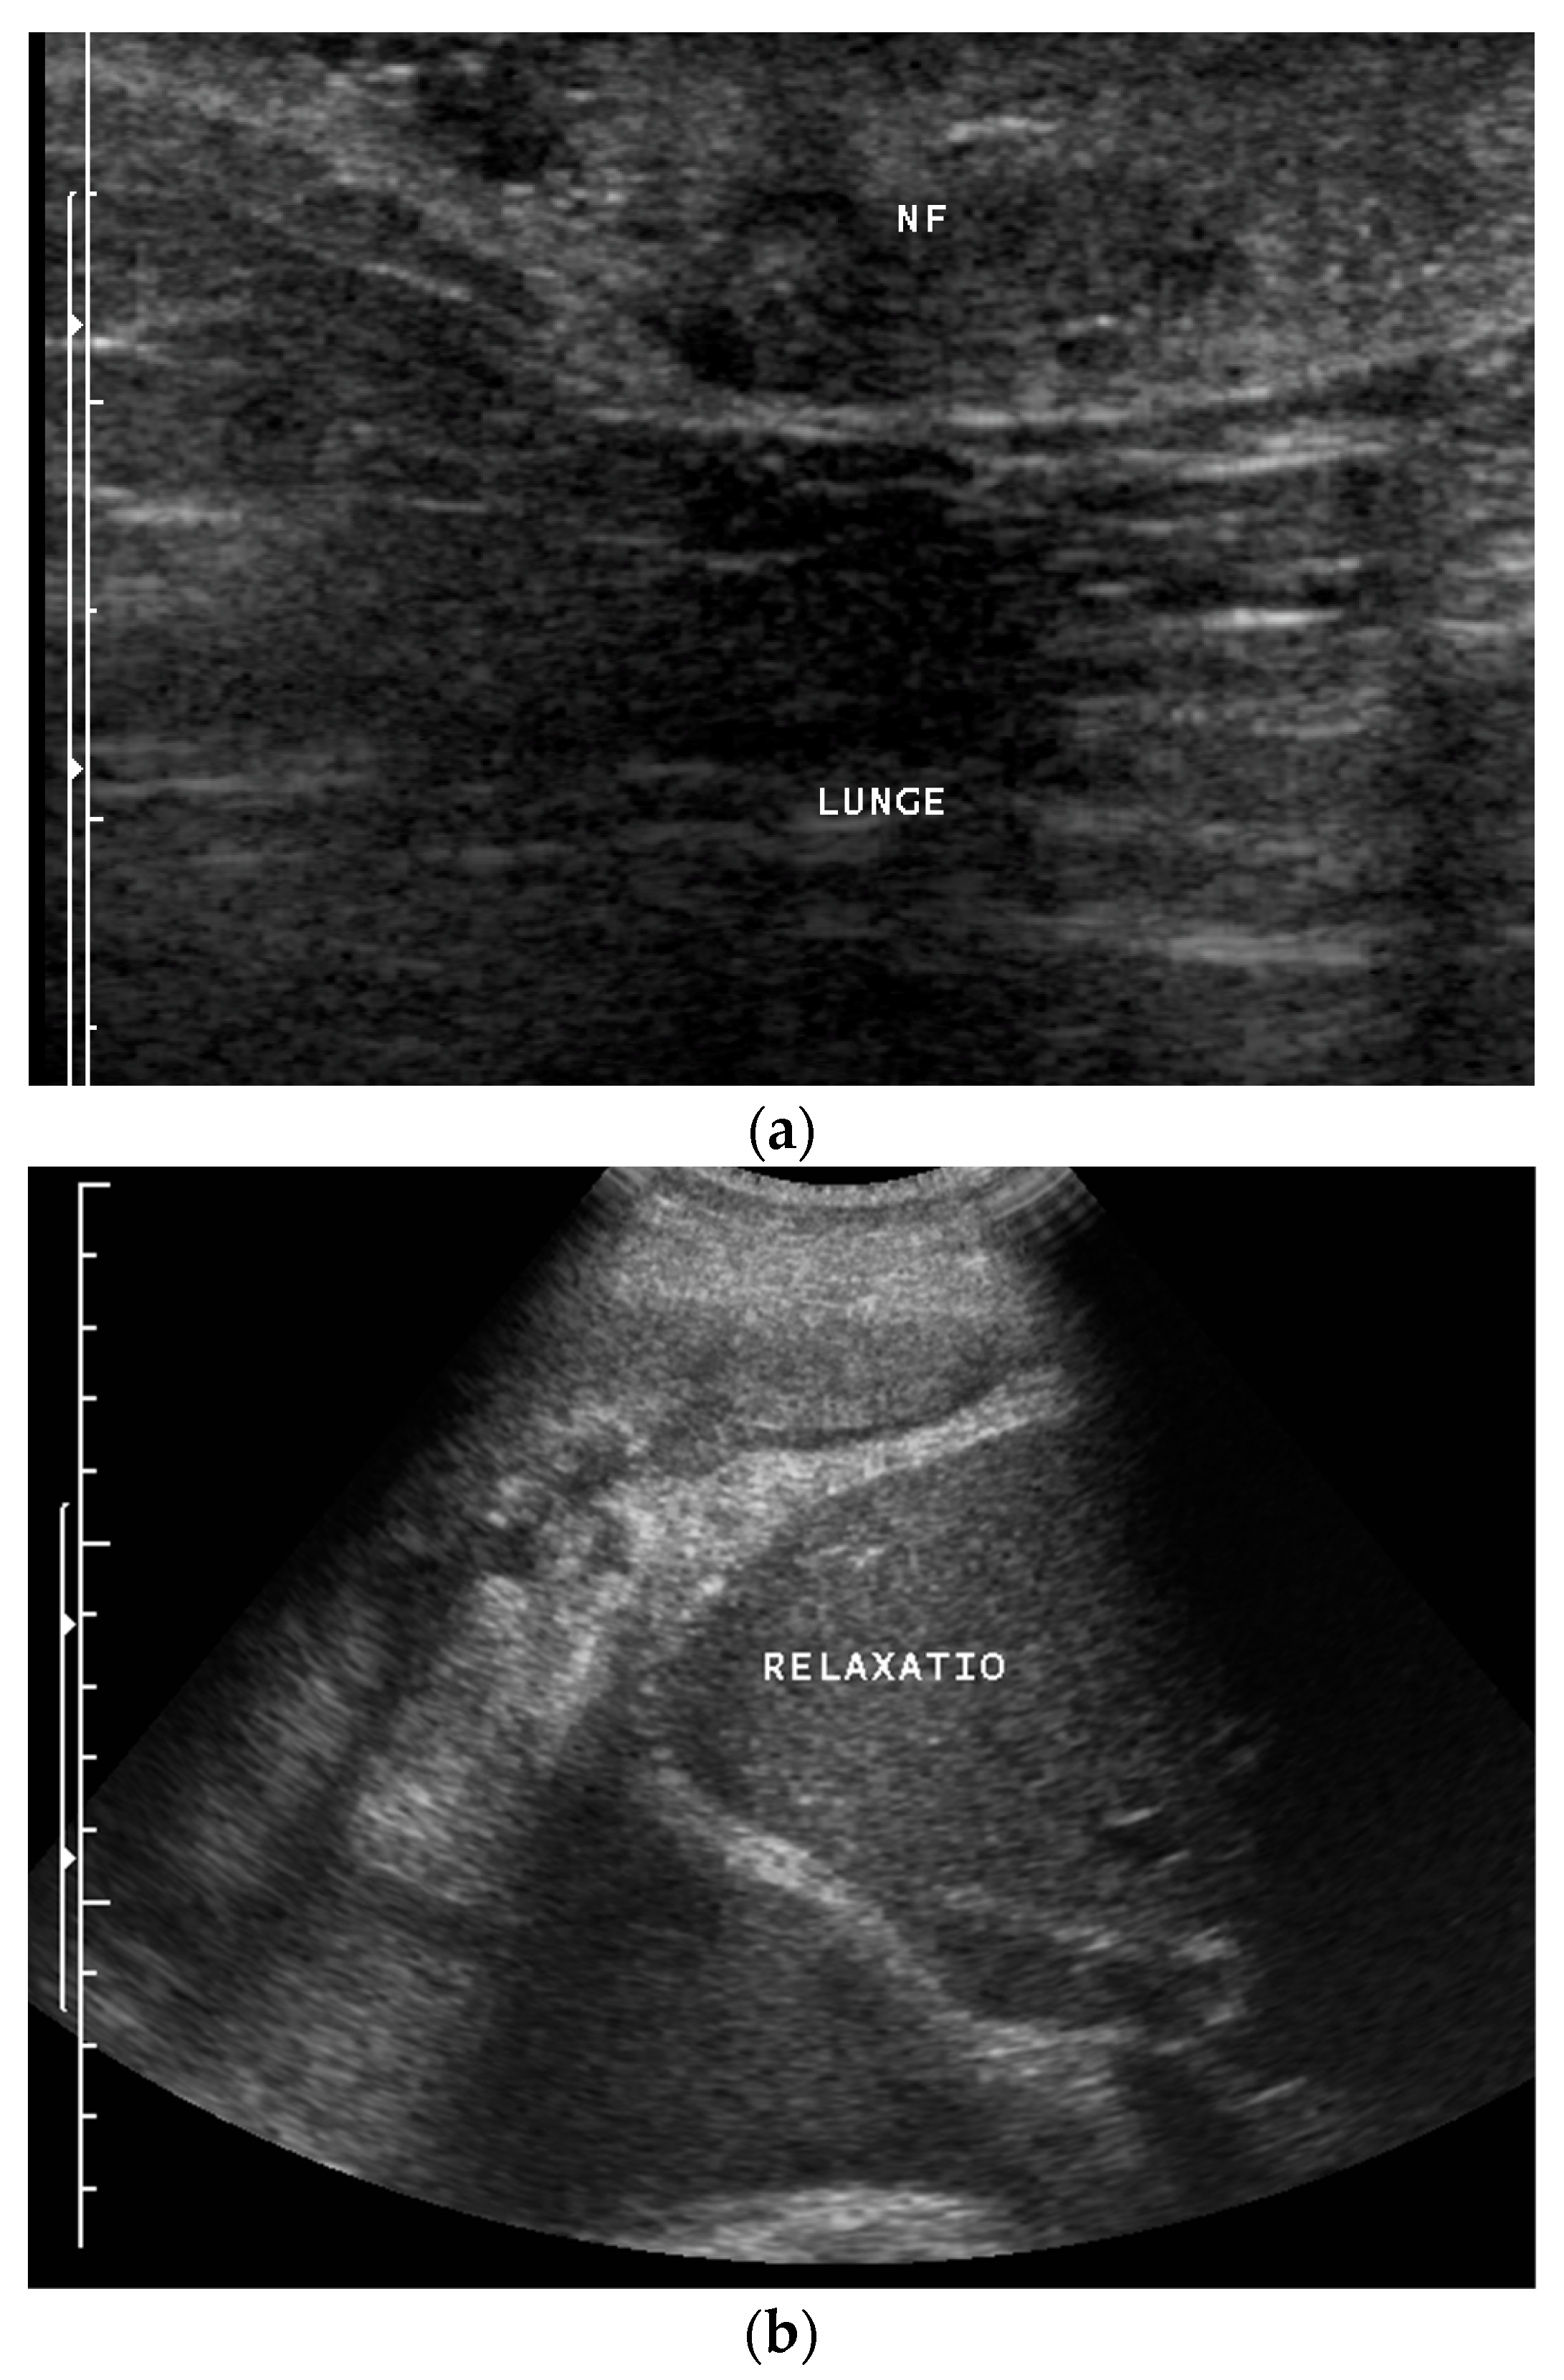

3. Pleural Mesothelioma